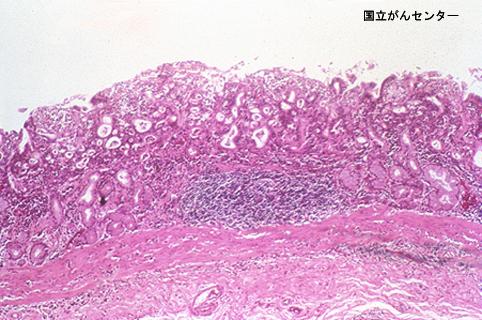

Criteria of Hist.ClassificationMalignant epithelial tumor/Adenocarcinoma

LocationStomach/Body

Technique, MethodHistology

Macroscopic TypesType 0/IIb (IIb+IIc) Superficial flat and depressed type

Size40 -

Depth of Tumor Invasionsubmucosa